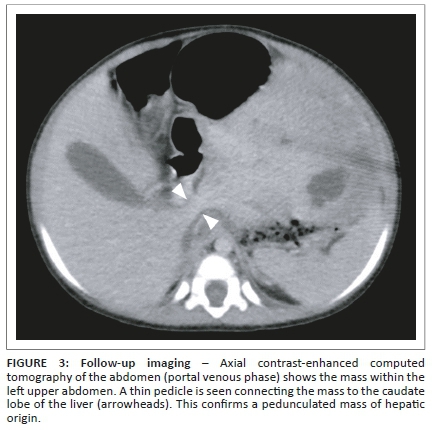

The child was referred to a tertiary institution for further management. Because of delay in follow-up, a repeat abdominal CT was performed approximately 4 weeks after the initial study. This was carried out to evaluate for interval growth and assist in surgical planning. It revealed the mass to have shifted into the left-sided abdomen, completely separable from the right and left liver lobes, with displacement of the bowel to the right (Figure 2). A thin pedicle could now be identified connecting the mass to the caudate lobe of the liver (Figure 3). The mass showed no interval change in size. A pedunculated hepatic mesenchymal hamartoma was confidently diagnosed, with no need for further imaging. Given the lack of markedly raised AFP levels, a hepatoblastoma was a less likely, however, still important in the differential diagnosis.